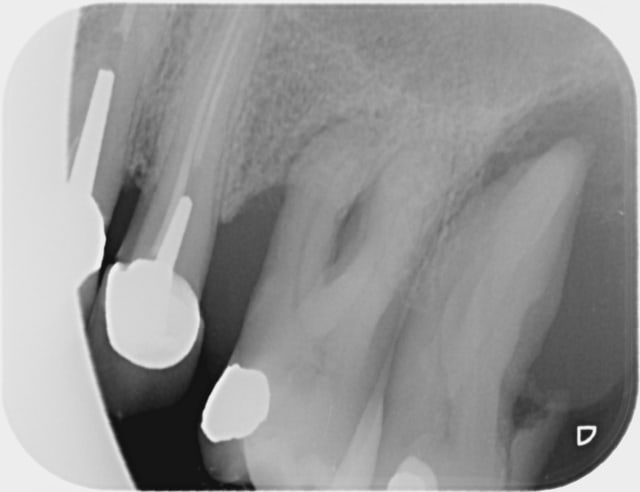

Bref , 10 mn de plus...laize béton , prochaine radio et explication madame .

Aujourd'hui , 20 mn de palabre autour de la radio...

Result : C , z6 , sc12 .(j'ai détartré le reste pas la 26 , ni la 27 , hin , oh !)

Moralité : p'tain , j'ai fait une erreur de diagnostic , point barre . J'ai pas vu que la 26 est conservable . Que les 2 sont égressées et que 2 dents de grande valeur fonctionnelle , même avec la 6 à 30 degré , la 7 à 80 , avec une gencive mandibulaire , bin...on mange avec !